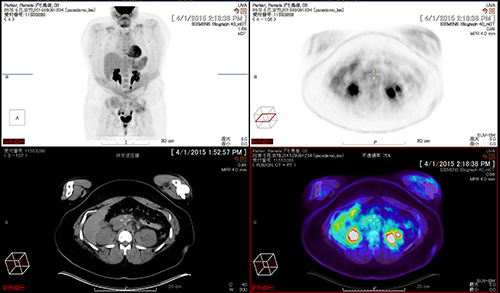

撮影画像の参照から,3Dデータの表示・解析までを実現する読影対応の「Vue PACS Client」は,自動位置合わせ,病変管理や,多数の解析機能で読影医をサポートします。臨床機能としては,PET/CTやCTパフュージョン解析,MRディフュージョン解析,マンモグラフィのトモシンセシス読影といった機能を搭載。効率的なPACS読影ワークフローをご提供します。